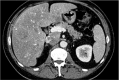

Patients with retroperitoneal sarcoma can present to a variety of clinicians with non-specific symptoms and retroperitoneal sarcomas can be incidental findings. Failure to recognize retroperitoneal sarcomas on imaging can lead to inappropriate management in non-specialist centers. Therefore it is critical that the possibility of retroperitoneal sarcoma should be considered with prompt referral to a soft tissue sarcoma unit. This review guides clinicians through a diagnostic pathway, introduces concepts in response assessment and new imaging developments.